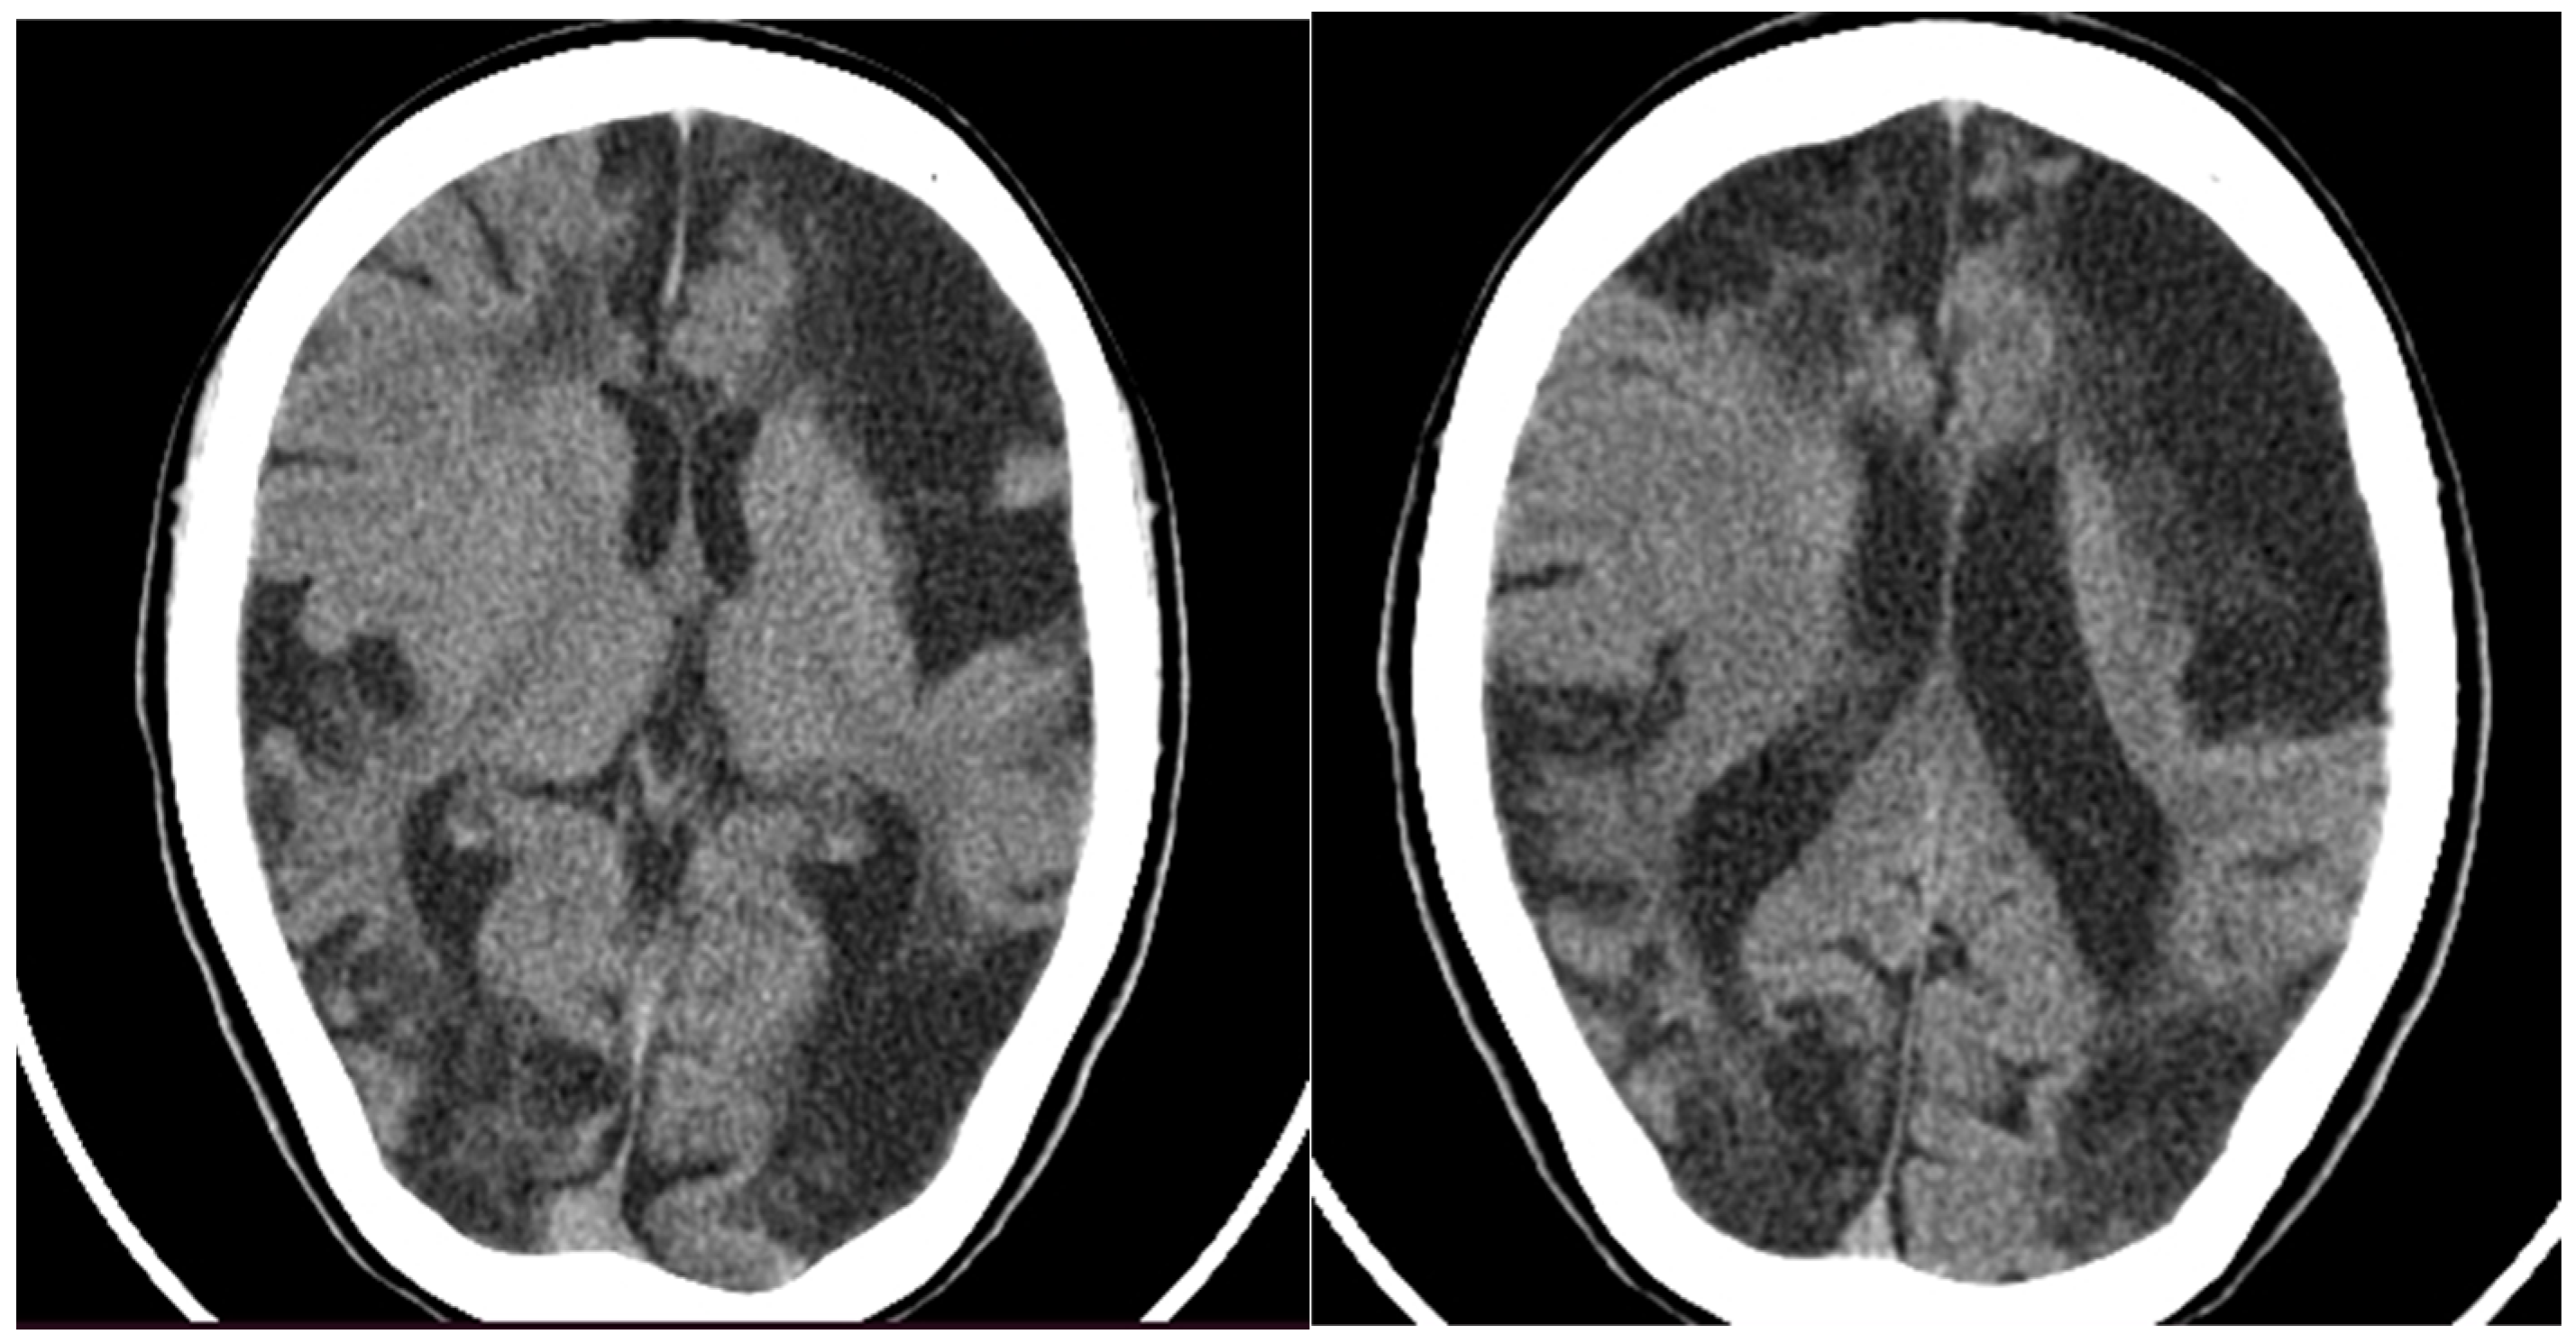

Later the same year, the child was hospitalized in a pediatric neurology department, where a CT of the head was performed (Figure 2), showing large hypodense areas with cerebrospinal fluid density, predominantly in the left hemisphere, smaller hypodense areas in the right hemisphere, and ventriculomegaly. A screening panel for autoimmune disorders was performed, including anticardiolipin antibodies, rheumatoid factor, antinuclear antibodies (ANA), ds-DNA antibodies, anti-Smith antibodies, anti-Ro (SS-A) and anti-La (SS-B) antibodies, and p- and c-ANCA- antibodies, with only the VDRL anti-cardiolipin antibodies testing slightly positive. Furthermore, mitochondrial disease screening revealed a mutation in the MT-ND2 gene, which was not reported to be pathogenic. At that time, treatment with pentoxifylline and piracetam was initiated, leading to a temporary improvement in weakness and speech; no new emergence of cerebrovascular symptoms occurred.

Figure 2. CT of the head showing large hypodense lesions in the (left) hemisphere and smaller ones on the (right).